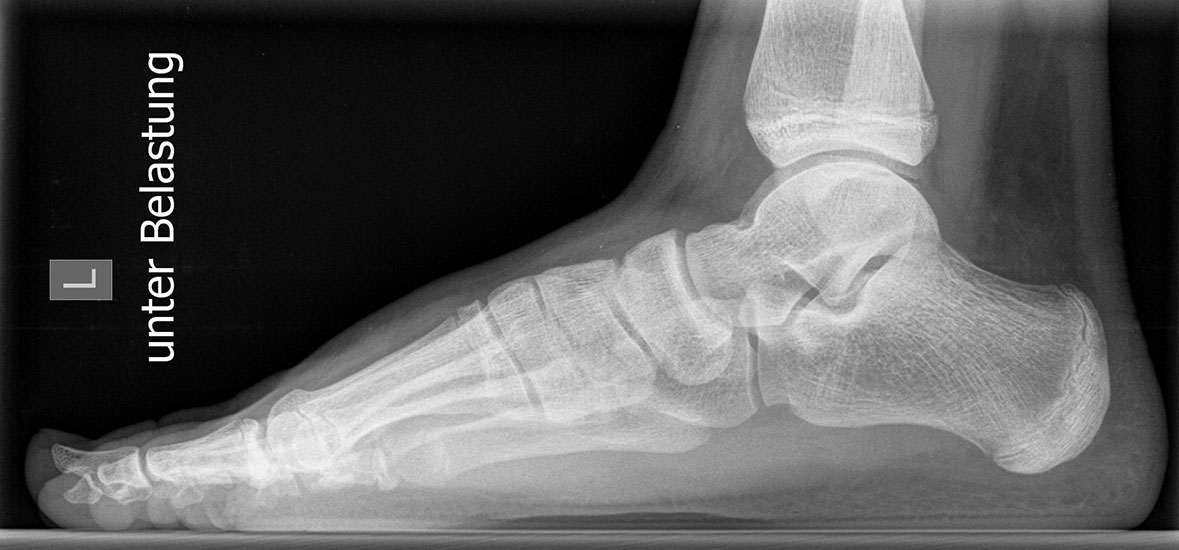

Röntgen

Standard ist die belastete Röntgenaufnahme des Fußes dorso-plantar und seitlich. Günstig ist eine Röhrenkippung von 10°-20°, um die Gelenke der Lisfranc-Linie einsehen zu können.

Ergänzend kann eine Schrägaufnahme hilfreich sein. Bei Metatarsalgien oder Pathologien der Sesambeine liefert die Sprinteraufnahme zusätzliche Informationen. Bei einer Pes planovalgus Fehlstellung wird ergänzend ein Saltzman view durchgeführt.

• Elevation/ Plantarisierung I. Strahl

CT, MRT, Szintigraphie, Sonographie oder andere ergänzende Untersuchungen sind beim alleinigen Auftreten eines Spreizfußes und Hallux valgus meist nicht notwendig. Zur Beurteilung der gestörten Druckverteilung kann ergänzend eine Pedobarographie durchgeführt werden.